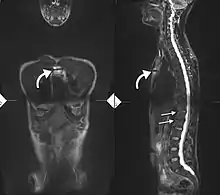

Lateral X-ray of the mid back in ankylosing spondylitis

Lateral X-ray of the neck in ankylosing spondylitis

T1-weighted MRI with fat suppression after administration of gadolinium contrast showing sacroiliitis in a person with ankylosing spondylitis